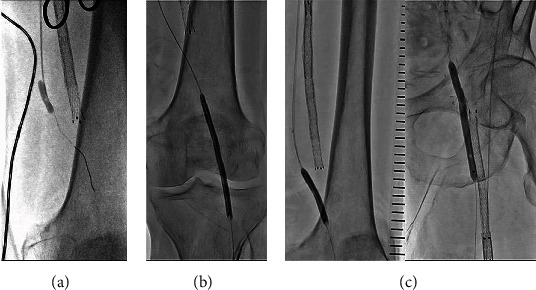

背景:先前的报道已经揭示了人工股腘动脉旁路闭塞(PFPBO)的各种血管内介入技术;然而,对于大多数介入医师和血管外科医生来说,PFPBO的治疗仍然具有挑战性,因为手术过程复杂。大多数报道的技术涉及装置植入。在本研究中,我们在不植入任何额外装置的情况下,对PFPBO进行了外科移植取栓和药物包被球囊血管成形术的联合治疗。此外,我们通过随访血管造影确定了这种治疗的良好长期结果。案例演示。一名77岁男性,有慢性肾脏疾病和冠状动脉疾病病史,左腿静止疼痛。在本次会诊的七年前,由于支架内左股浅动脉(SFA)闭塞,他接受了股腘动脉搭桥(fbp)手术。术后四年,超声扫描显示近端吻合口狭窄;因此,继续进行药物治疗。在目前的咨询中,诊断性血管造影显示FPB和髌下血管闭塞。在第一次再通的尝试中,导丝无法通过阻塞的SFA。因此,采用另一种技术来重建FPBO和腘窝下血管。我们通过右股总动脉(CFA)插入引导鞘后进行了左腿血管造影。首先,通过暴露的左侧CFA使用Fogarty导管进行手术取栓。在通过右侧CFA进行血管内治疗后,我们对吻合口狭窄和闭塞的腘下血管进行了药物包被球囊血管成形术。随访血管造影未见再狭窄。在进一步的随访血管造影中,义肢近端吻合口残余狭窄明显消退。结论:这种新的血运重建策略可能是治疗PFPBO的一种可行的选择。

Background: Previous reports have revealed various endovascular intervention techniques for prosthetic femoropopliteal bypass occlusion (PFPBO); however, treatment for PFPBO remains challenging for most interventionalists and vascular surgeons because the procedure is complicated. Most of the reported techniques involve device implantation. In the present study, we performed a combination of surgical graft thrombectomy and drug-coated balloon angioplasty for PFPBO without implanting any additional devices. Furthermore, we determined the favorable long-term results of this treatment using follow-up angiography. Case Presentation. A 77-year-old man with a history of chronic kidney disease and coronary artery disease presented to our clinic with rest pain on his left leg. Seven years prior to the current consult, he underwent femoropopliteal bypass (FPB) surgery using a prosthetic graft due to in-stent occlusion of the left superficial femoral artery (SFA). Four years after surgery, a duplex ultrasound scan revealed stenosis of the proximal anastomosis site; hence, medical therapy was continued. On the current consult, diagnostic angiography revealed occlusion of the FPB and infrapopliteal vessels. In the first attempt at recanalization, the guidewire was unable to pass through the occluded SFA. Therefore, another technique was performed to revascularize the FPBO and infrapopliteal vessels. We obtained an angiography of the left leg after inserting the guiding sheath via the right common femoral artery (CFA). First, surgical thrombectomy using a Fogarty catheter via the exposed left CFA was performed. Following endovascular therapy via the right CFA, we performed drug-coated balloon angioplasty for anastomotic stenosis and recanalized occlusive infrapopliteal vessels. Restenosis was not observed on follow-up angiograms. On further follow-up angiography, there was notable regression of the residual stenosis at the proximal anastomosis of the prosthetic graft.